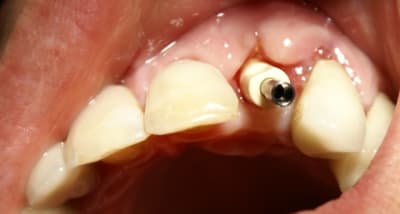

Pour ceramik, l'implant est un Xive 3.8 dans le premier cas et un 3.4 dans le second (peut être un peu sous-dimentionné d'ailleurs).

Excellente stabilité primaire avec ces implants que je préfère aux straumann, easy et ankylos.

Tout à fait d'accord growler et c'est d'ailleurs ce que l'on peut voir sur le cas suivant. Fracture radiculaire, aucune infection periradicualire. Extraction et implantation immediate. Espace existant entre l'implant et l'alvéole est comblé par du BioOss. Un logement sous gingival est formé en vestibulaire et palatin de facon à pouvoir recouvrir le tout par BioGide et un conjonctif enfoui.

L'implant est de 15mm mais l'alvéole était large et 50% environ de la surface implantaire n'était en contact qu'avec du BioOss. J'ai pour cela préféré enfouir.